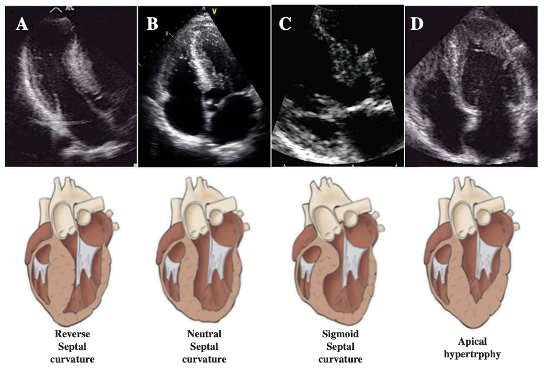

3/HCM is defined as LV wall thickness of ≥15 mm that is not explained by loading conditions (e.g., hypertension, valvular, congenital disease) or infiltrative cardiomyopathies.

cardionerds.com/cardsjc-hypert… @KateAltaWilcox 🙌🏽, #HouseTaussig 💪🏽 Image PMID: 26567960